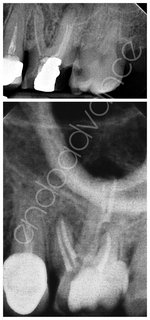

Αρχική ενδοδοντική θεραπεία σε κάτω γομφίο με 3 ρίζες (radix entomolaris)